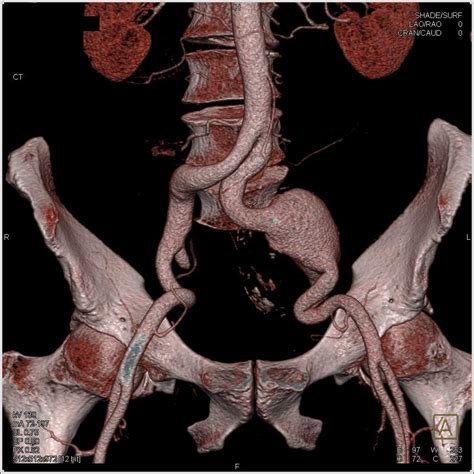

Diagnosing an Iliac Artery Aneurysm typically involves a combination of medical history, physical examination, and imaging tests. The diagnostic process may include:

• Computed Tomography Angiography (CTA): This imaging test provides detailed images of the blood vessels and can help determine the size and location of the aneurysm.

• Endovascular Repair: This minimally invasive procedure involves inserting a stent-graft through a small incision in the groin and guiding it to the site of the aneurysm. The stent-graft reinforces the weakened artery wall and prevents rupture.